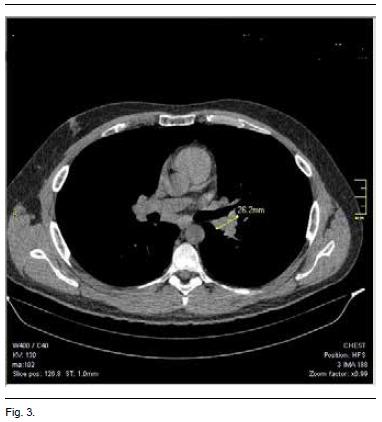

Se complementó con tomografía de tórax que evidencia adenopatías hiliares bilaterales y paratraqueales altas y bajas a derecha, que no forman conglomerados (Figura 2).

A los 2 meses del alta el paciente se encuentra asintomático. Se realizó una TAC de tórax de control, que muestra una disminución importante del tamaño de las adenopatías (Figura 3). A la fecha, el paciente no ha mostrado signos de recidiva, y se inició el descenso de la dosis de corticoides.

El control evolutivo del paciente a los 2 meses mostró una franca disminución del tamaño de las adenopatías, acorde con la forma evolutiva de esta variante de sarcoidosis.